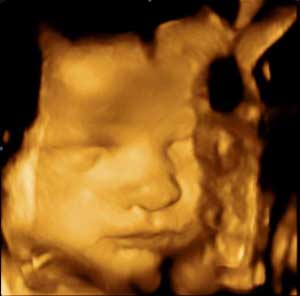

A naplóban a leendő, vagy már gyakorló szülők fotóikkal, ultrahang felvételeikkel illusztrálva tudják megörökíteni a babavárás, a nagy nap és az első közös napok minden mozzanatát.

A könyv segítségével a leendő szülők hétről-hétre megismerhetik és közel 100 db 3 dimenziós ultrahang fotón nyomon is követhetik a Pocaklakó fejlődését.

- A magzat fejlődése hétről-hétre 3D-s fotókkal illusztrálva és a kismamára váró vizsgálatok az adott hónapban

A könyvben található ultrahang képek MEDISON 4D ultrahang készülékkel készültek.